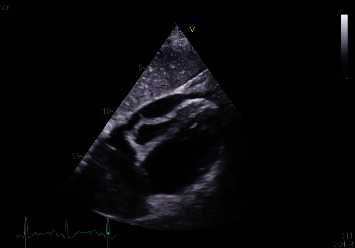

霍奇金淋巴瘤(HL)是一种不常见的恶性肿瘤,以霍奇金细胞或里德-斯特恩伯格细胞为特征。HL 对心脏的影响仍然是研究最少的主题之一。文献中关于 HL 患者心脏填塞的病例报告很少。我们描述了一例 21 岁女性患者的病例,她以心脏填塞作为 HL 的首发症状。任何心包积液都可能导致心包填塞,因此需要立即引流并进行液体分析以进行彻底检查。迅速识别和及时干预是有效处理这些复杂情况的关键。因此,临床医生应提高对此类病例的认识。

Hodgkin lymphoma (HL) is an uncommon malignancy that is characterized by Hodgkin or Reed-Sternberg cells. Cardiac implications of HL remain one of the least investigated subjects. There are few case reports in the literature of cardiac tamponade in HL patients. We describe a case of a 21-year-old female patient who presented with cardiac tamponade as an initial presentation of HL. Any pericardial effusion significant for tamponade requires immediate drainage and fluid analysis for thorough investigation. Prompt identification and timely intervention are crucial in effectively addressing these complex situations. Therefore, clinicians should maintain heightened awareness in such cases.